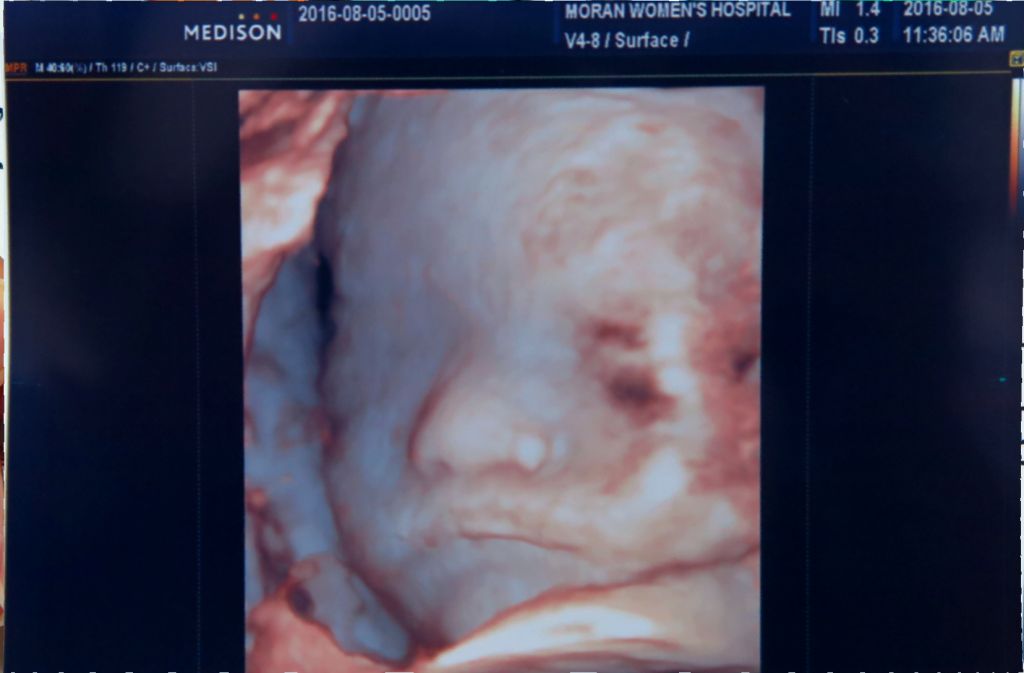

지난번 검사때 부끄럼쟁이 별이가 얼굴을 손으로 가려서 얼굴이 제대로 나오지 않아 새로 사진 찍으러 갔습니다.

별이는 이번에도 손과 탯줄로 얼굴을 가리려 노력하였지만ㅋㅋ 지난번 보다는 얼굴이 잘 나왔어요.

두달 전 사진과 비교하니 얼굴에 살이 붙어서 그런지 좀더 사람같아졌네요^^

입을 벌리고도 사진 한장 찍었는데 제 딸이라 그런게 아니라 귀엽네요.ㅎㅎ

근데 엄마 아빠 닮아서 코는 어쩔수가ㅠ 이래서 씨도둑질은 못한다 하는가 봅니다.

이번이 정밀 초음파 마지막이라 별이가 세상에 나온뒤에 얼굴 볼 수 있겠네요.